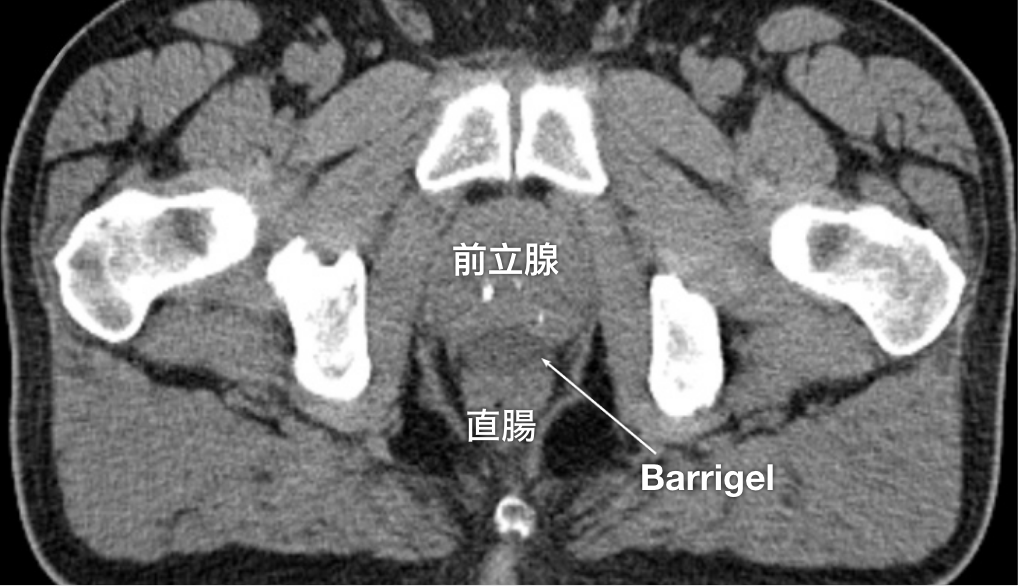

CT画像

CT画像提供:Gregory Bell, MD

Interventional Radiologist; Texas, United States